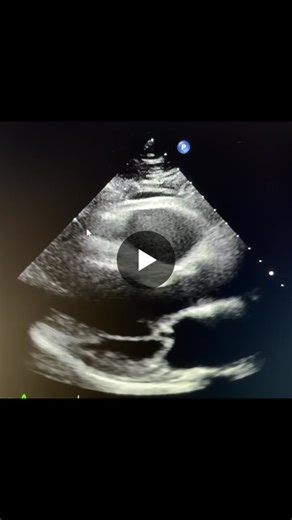

Severe mitral regurgitation (MR) caused by a flail of the posterior mitral leaflet (PML) is a significant clinical finding. In the world of cardiology, flail is a step beyond simple

Severe mitral regurgitation (MR) caused by a flail of the posterior mitral leaflet (PML) is a significant clinical finding. In the world of cardiology, "flail" is a step beyond simple prolapse; it indicates a complete loss of structural support for the valve leaflet. A flail is almost always associated with severe MR because the coaptation (the ...

What is your diagnosis? Can you determine what the problem is fro

…